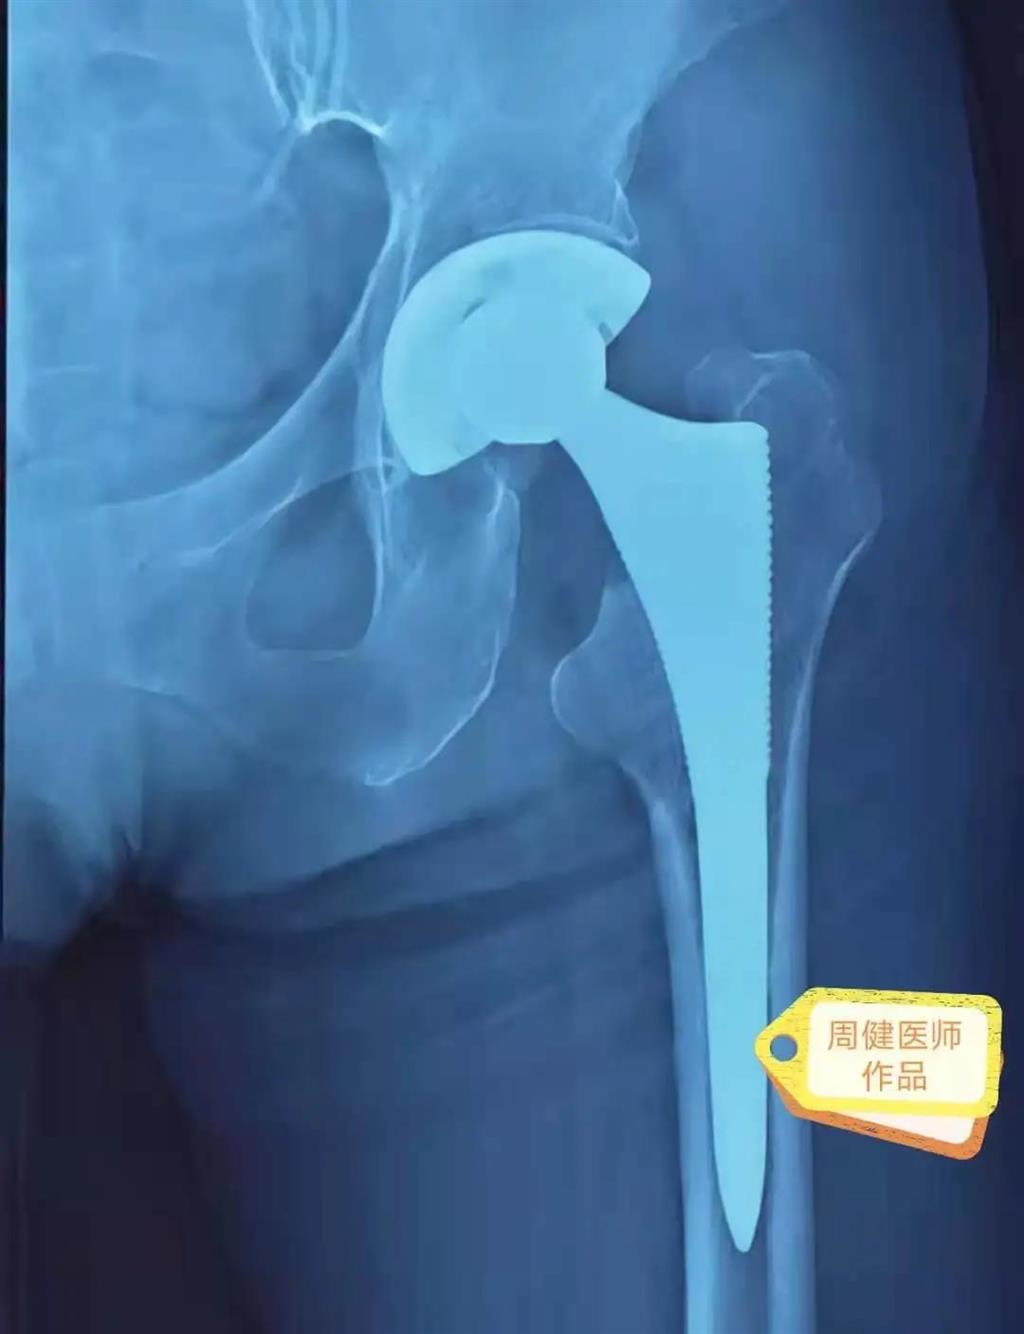

6月30日的“關(guān)節(jié)置換術(shù)”,患者是一位上了年紀(jì)的老人,苦于病痛折磨多年的他四處“求醫(yī)問藥”,最后在多位專家醫(yī)師及病友地力薦下選擇了和平國際醫(yī)院,在醫(yī)師團隊“偷天換日”般的手術(shù)后,老人成功告別了苦纏多年的病痛。

周健說,這場“關(guān)節(jié)置換術(shù)”對于他們團隊而言其實算是比較普通的手術(shù),因為做過很多同類的手術(shù),成功案例繁多,因此在手術(shù)操作上有較多地實操經(jīng)驗。“不過話雖如此,作為醫(yī)生我們對于每一場手術(shù)都會全力以赴,這是為醫(yī)者的職責(zé)也是義務(wù)。”